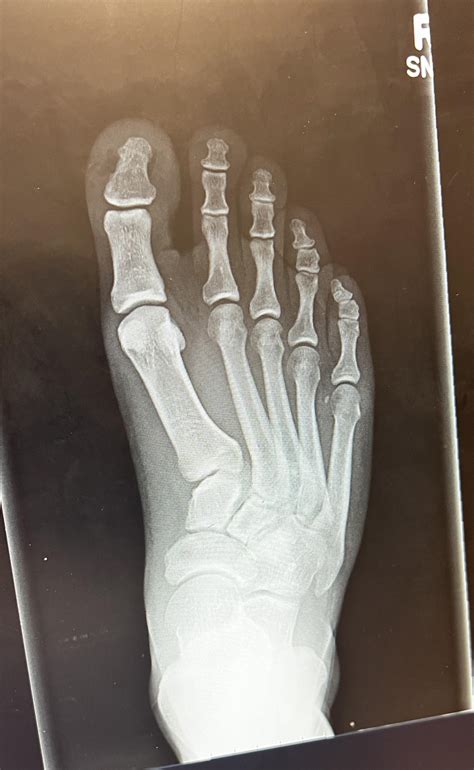

Anteroposterior (AP) View Shows the front of the foot, including the toes, metatarsals, and tarsal bones.

• normal foot x ray ap

• normal foot x ray adult